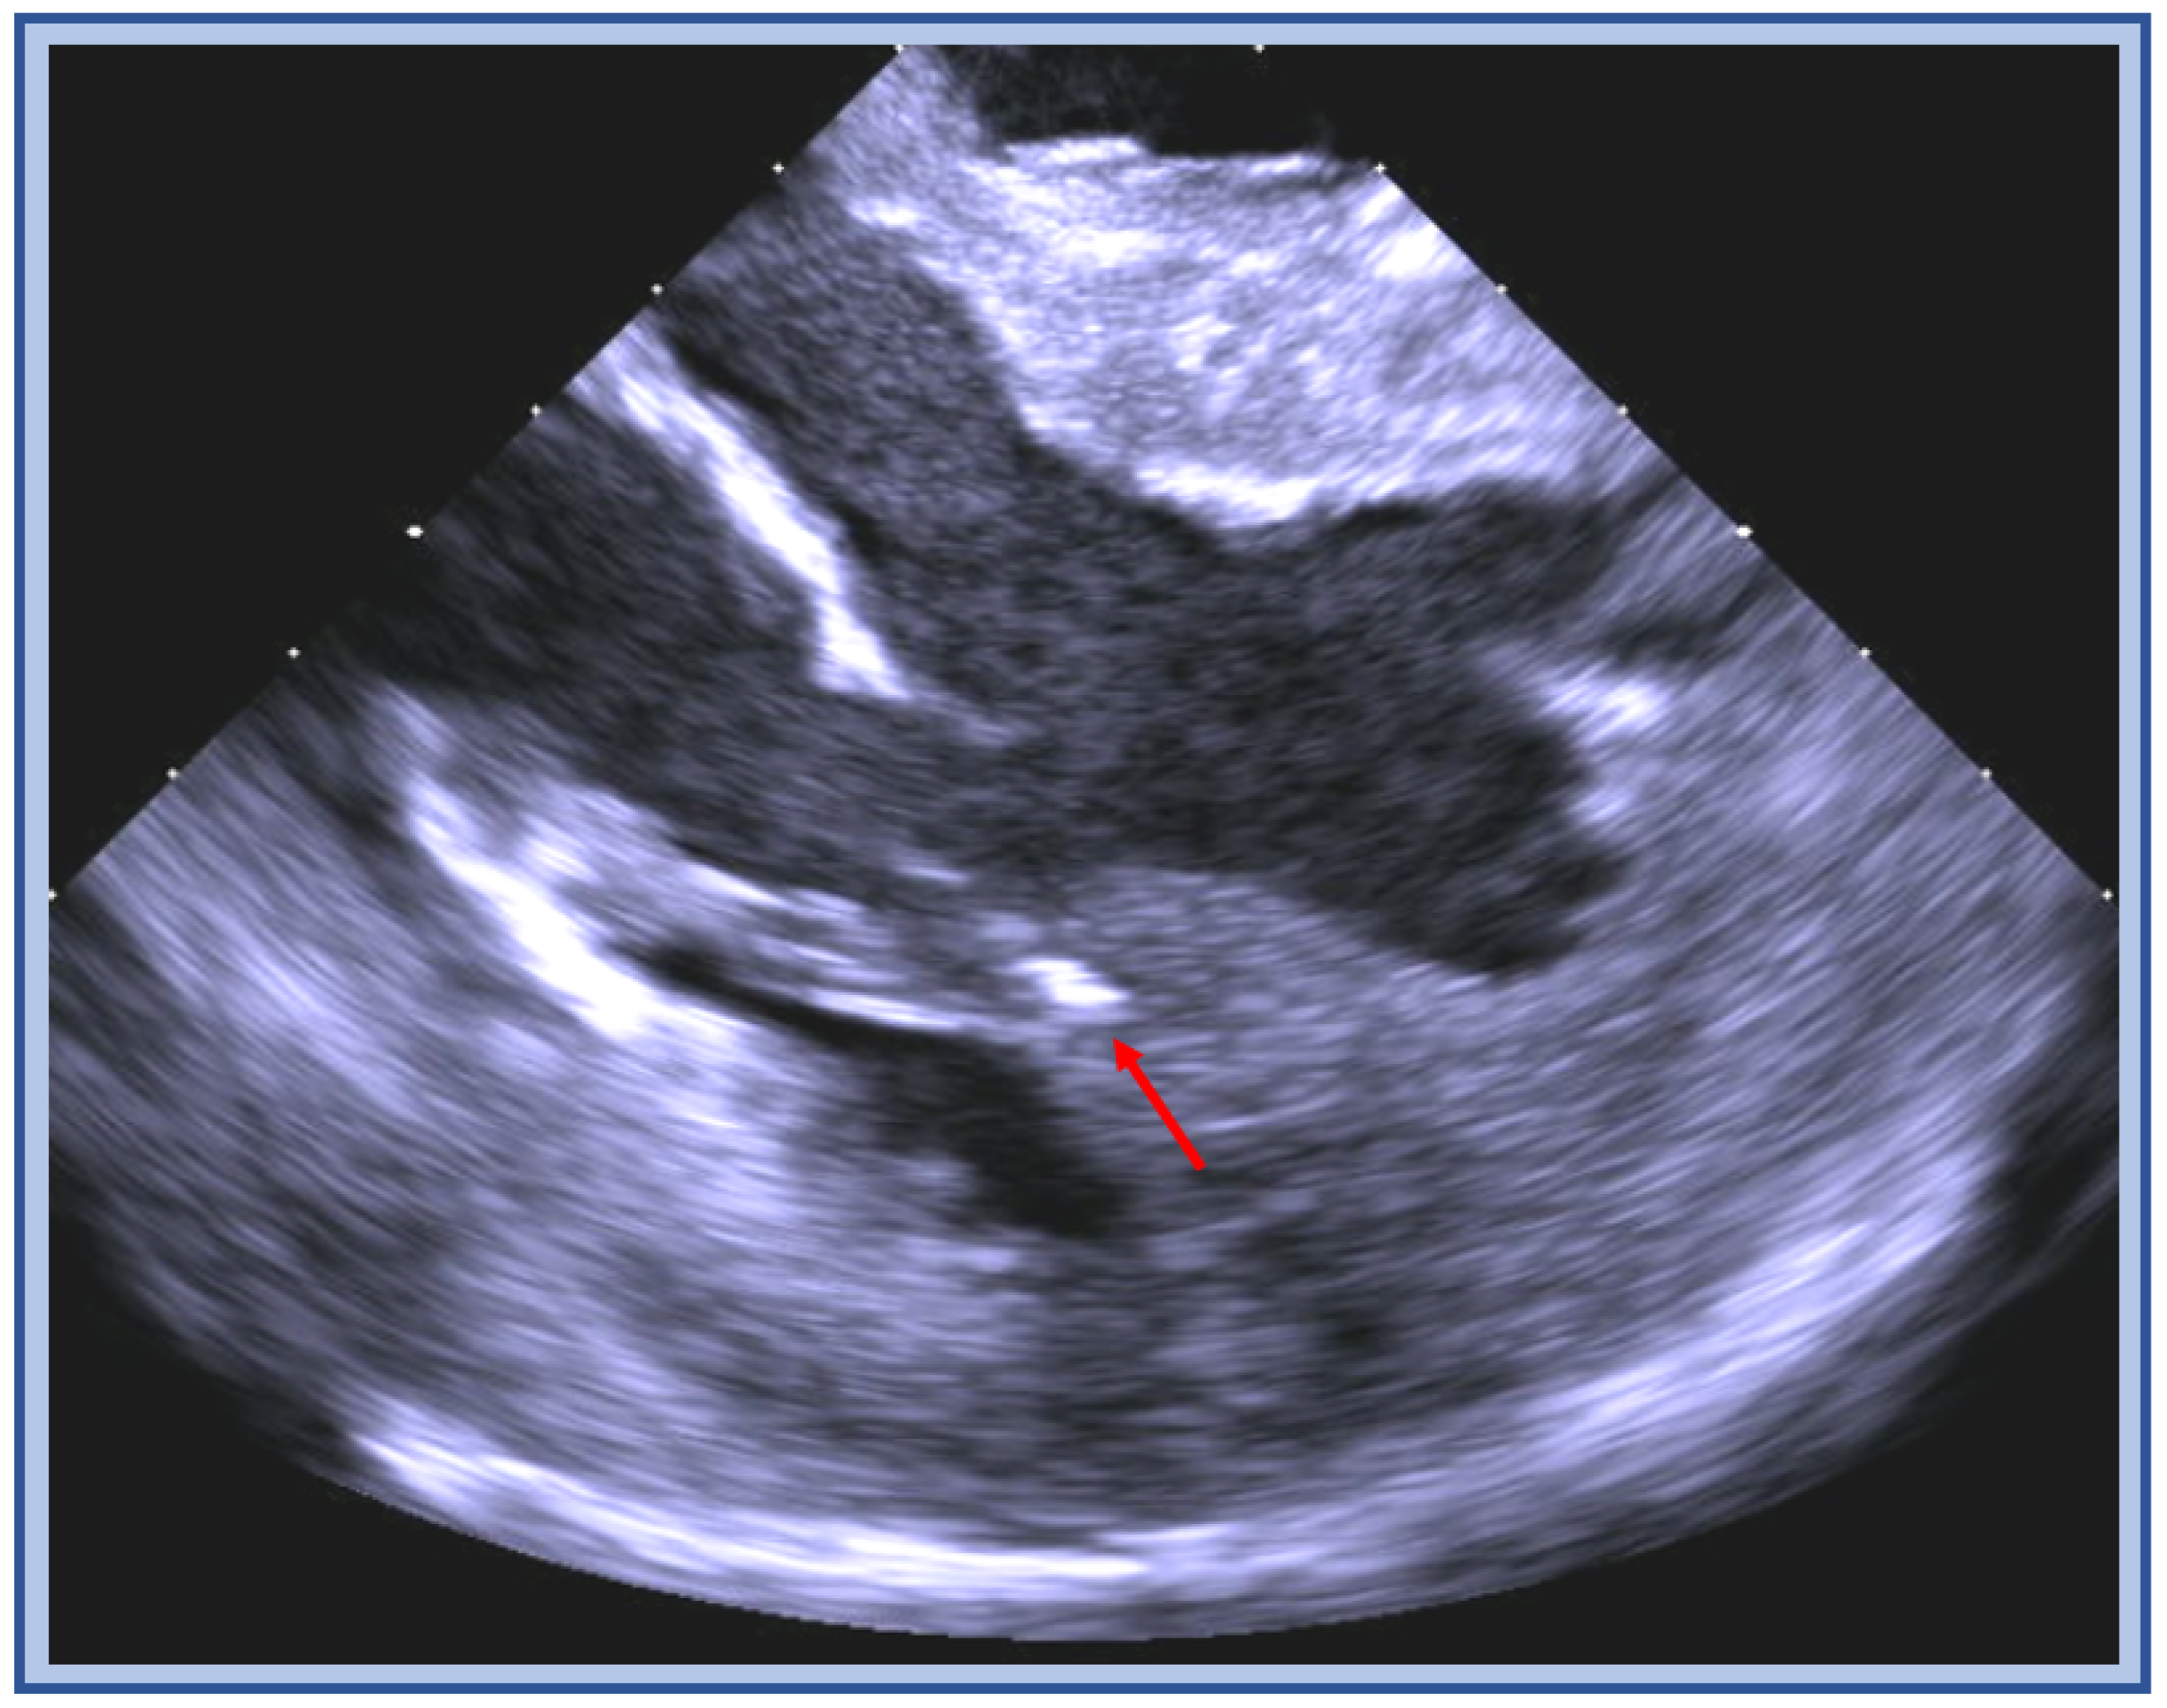

5. Papillary Muscle VT

5.2. Catheter Ablation Considerations